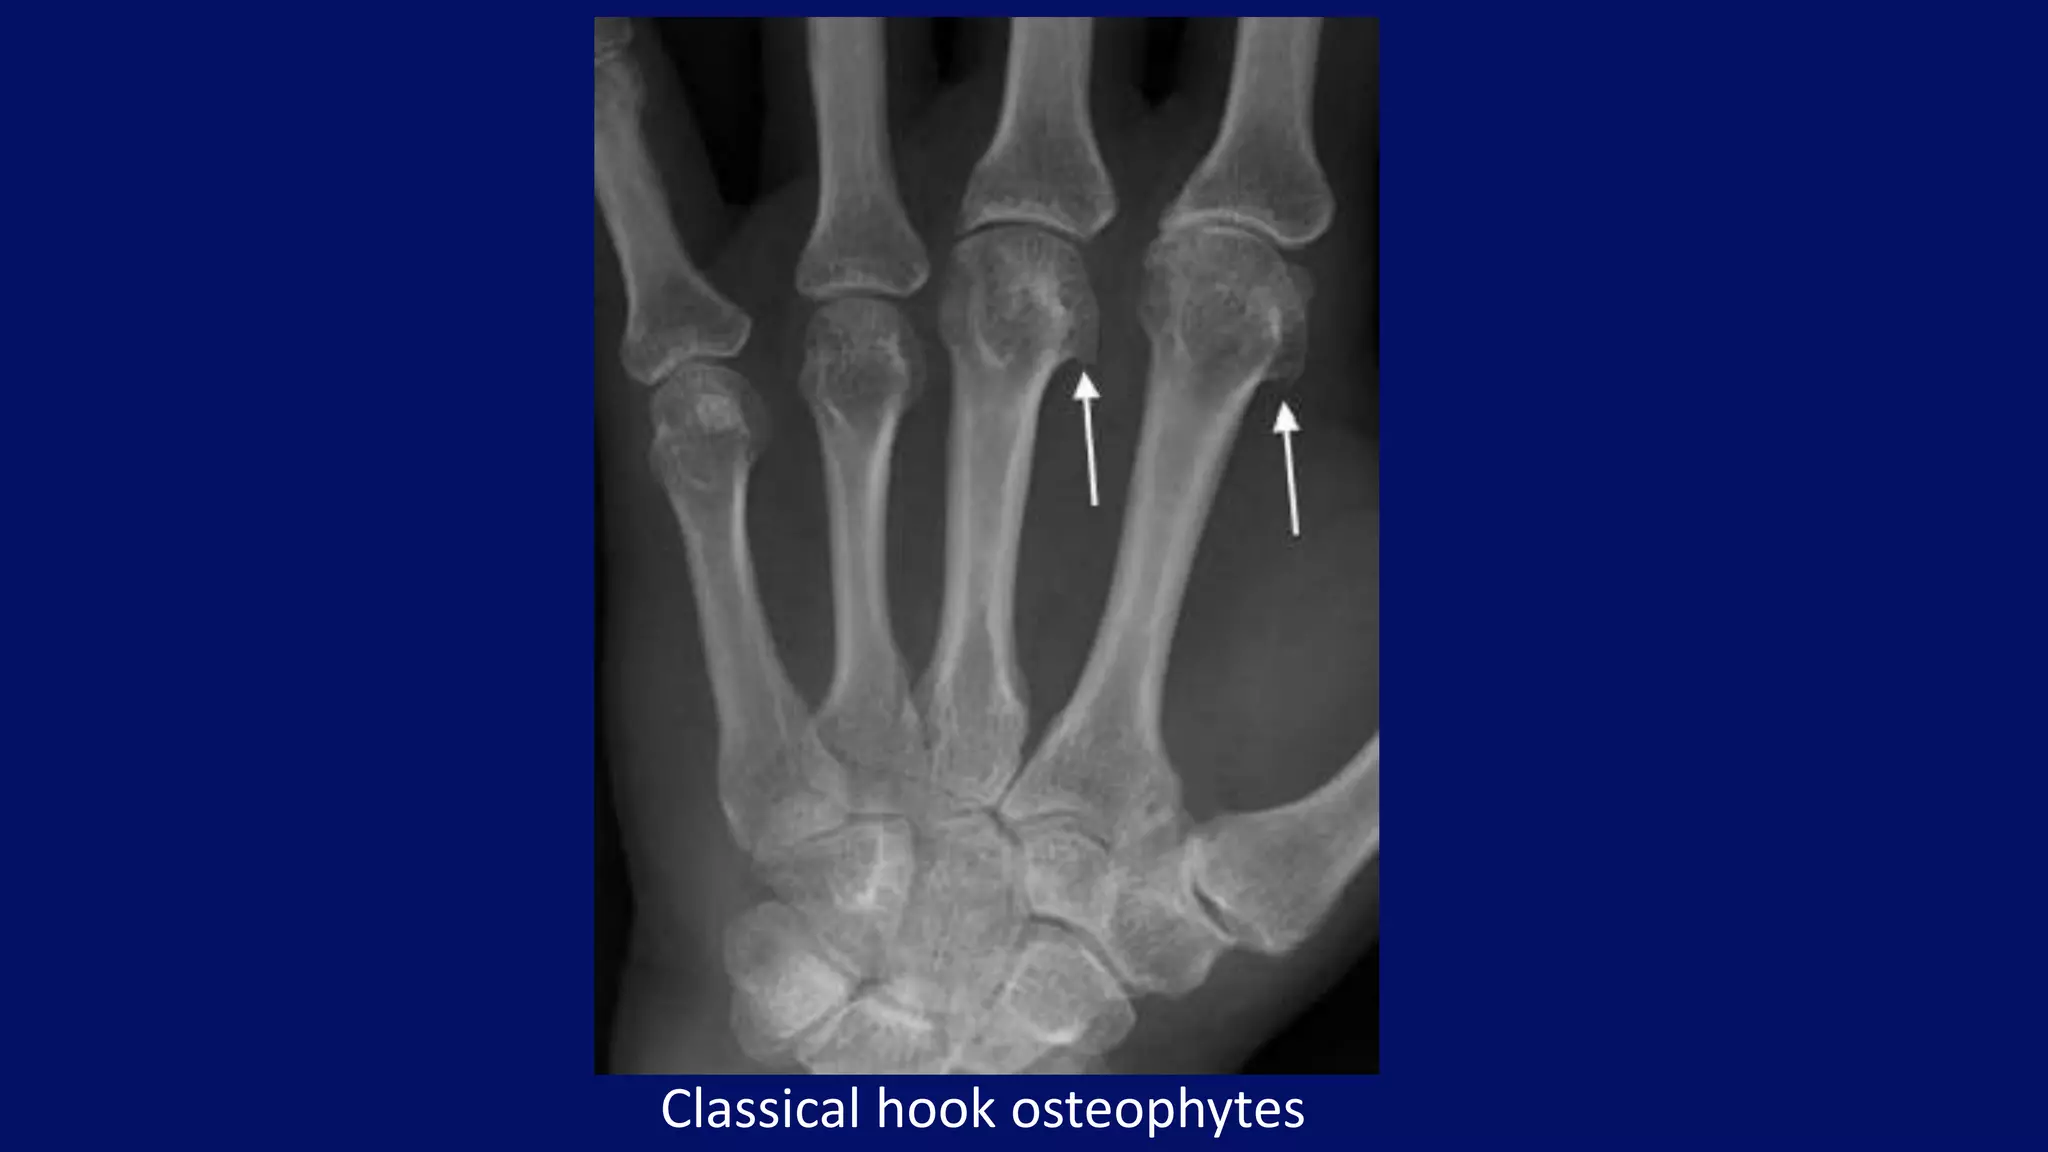

• hook-like osteophytes

Classical hook osteophytes

• #110 thers is relative sparing of IP joint with invovlment of MCP joints Another typical feature of the disease is the presence of hook-like osteophytes generally seen on the radial aspect of the metacarpal heads. Chondrocalcinosis is seen in association with the metacarpal changes, usually best appreciated in the wrist.

• #113 Patient with haemochromatosis demonstrating classical hook osteophytes arising on the radial aspects of the index and middle finger metacarpal heads (arrows).